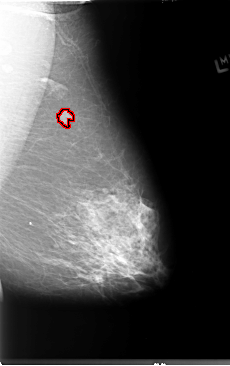

B_3080_1.LEFT_MLO

B_3080_1.LEFT_CC

FILE: B_3080_1.LEFT_MLO.OVERLAY

TOTAL_ABNORMALITIES 1

ABNORMALITY 1

LESION_TYPE MASS SHAPE LOBULATED-IRREGULAR MARGINS ILL_DEFINED

ASSESSMENT 4

SUBTLETY 4

PATHOLOGY MALIGNANT

TOTAL_OUTLINES 1

BOUNDARY

FILE: B_3080_1.LEFT_CC.OVERLAY

LESION_TYPE MASS SHAPE LOBULATED MARGINS ILL_DEFINED